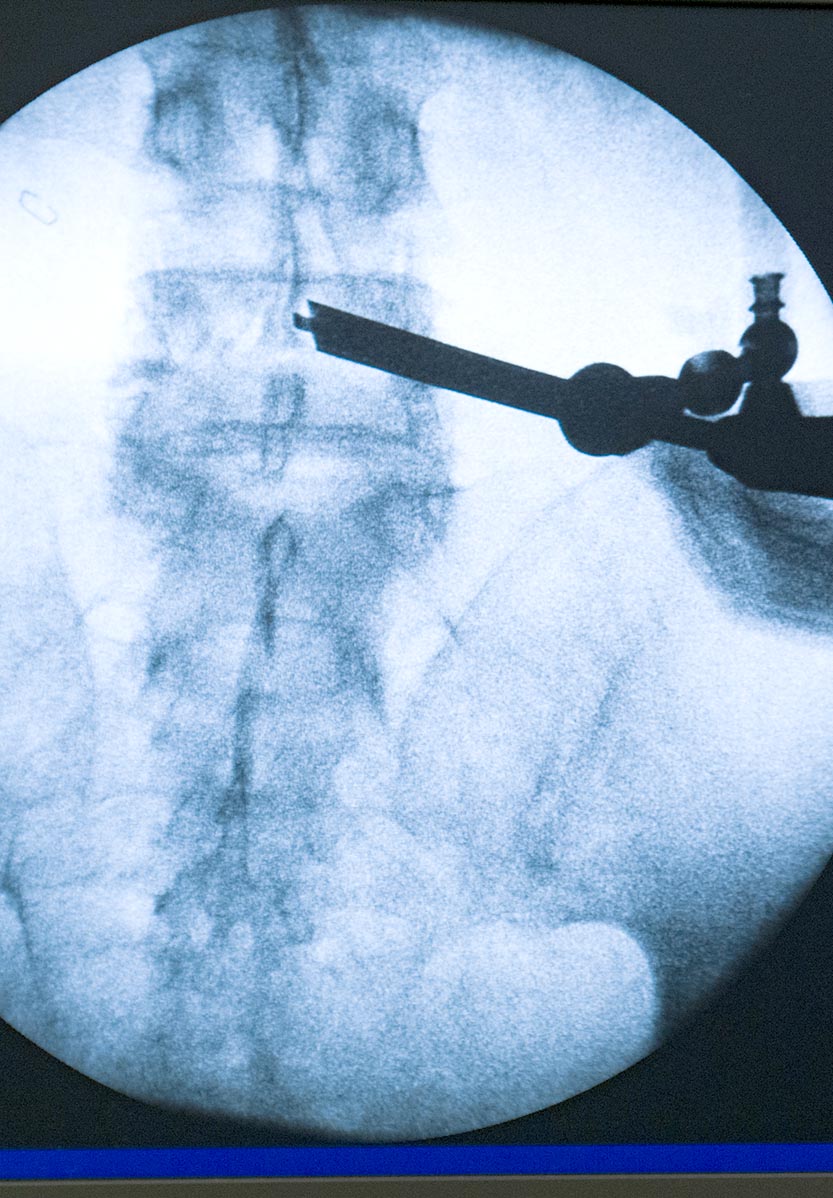

جراحات العمود الفقري المتقدمة

endoscopia avanzada de columna minimamente invasiva en madrid